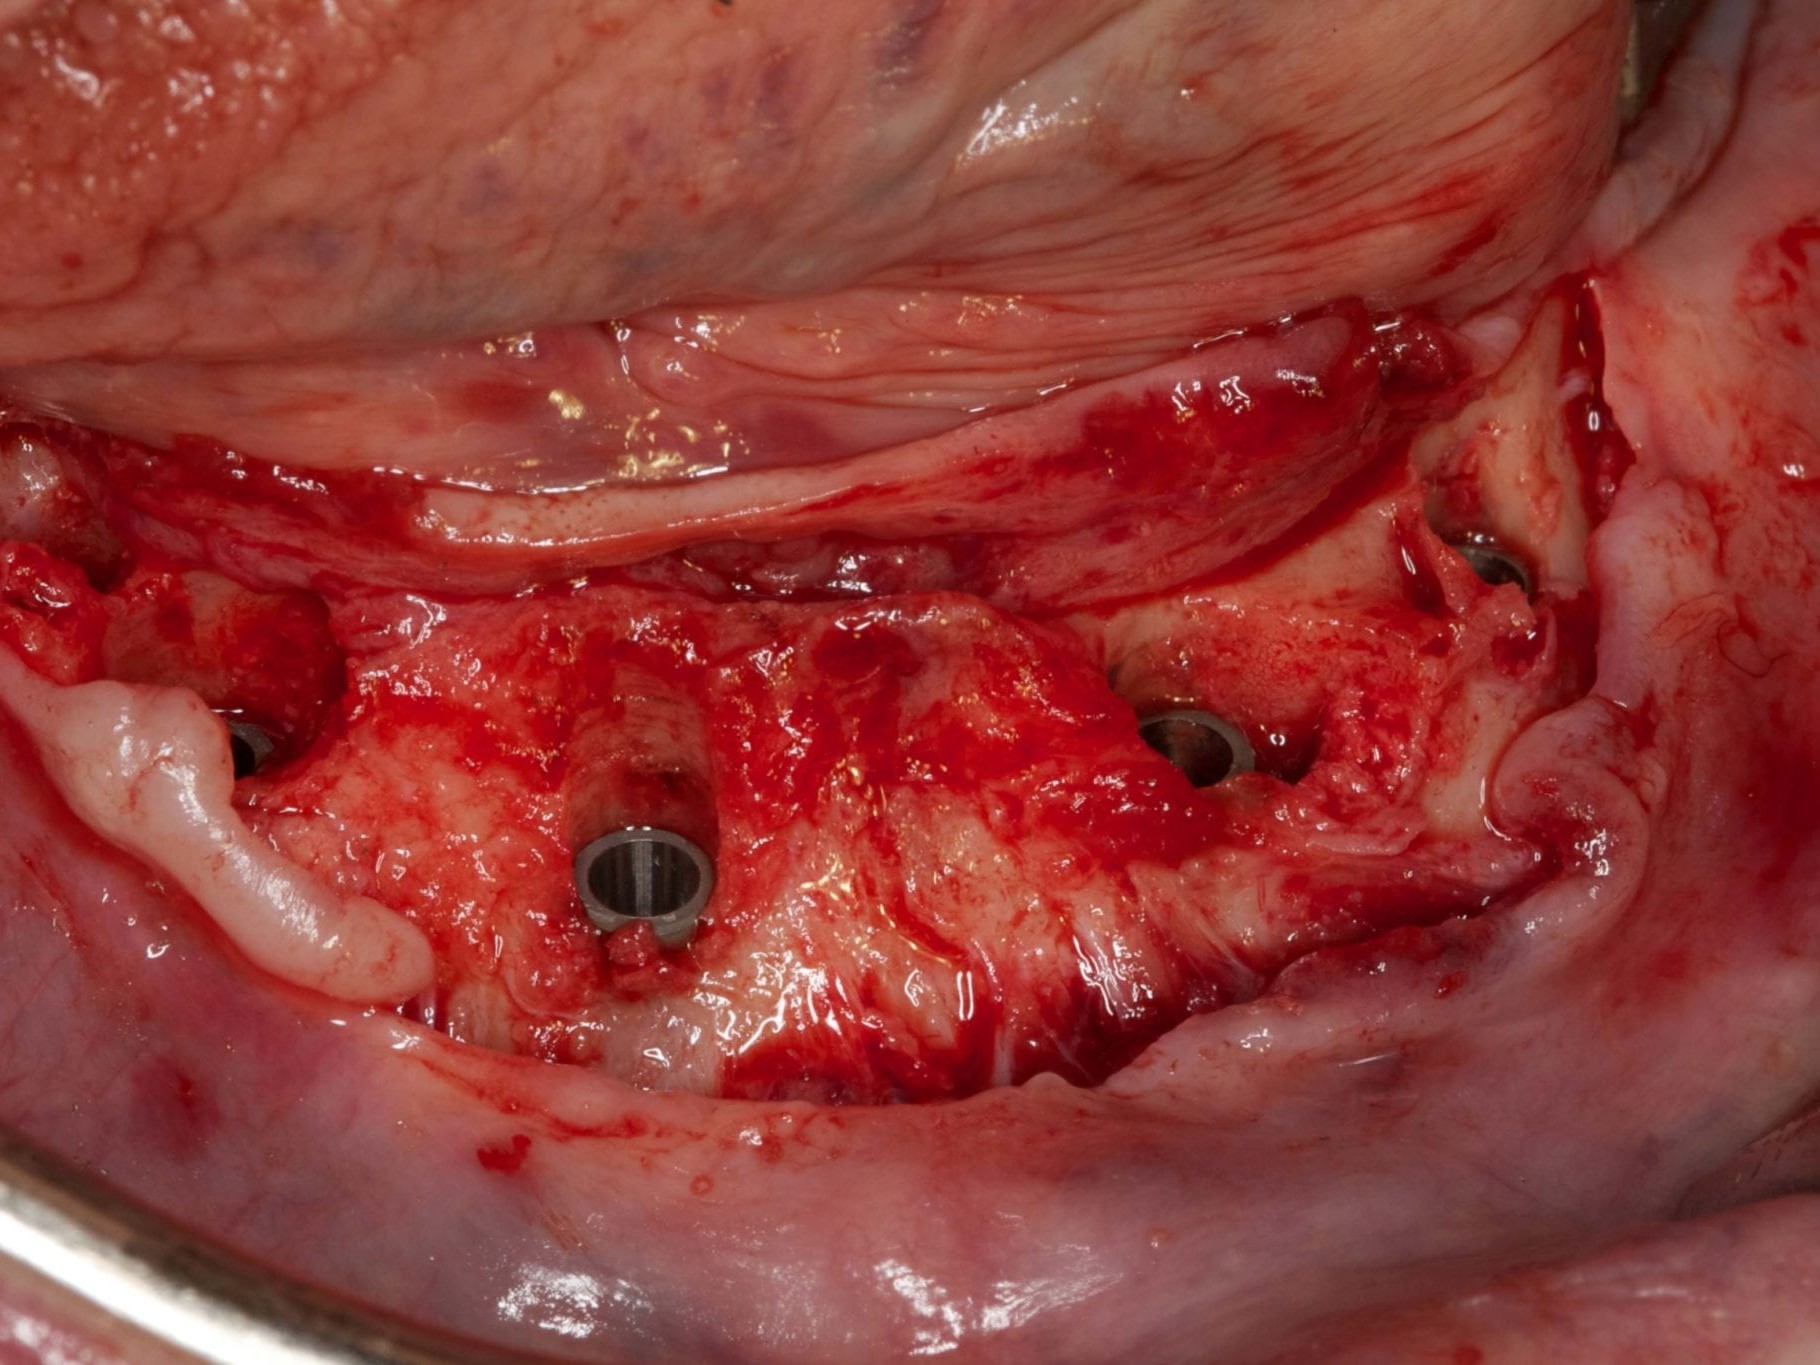

Für die Allgemeinanästhesie erfolgte zunächst die zusätzliche Gabe eines typischen Infiltrationsanästhetikums. Intravenös wurde unmittelbar präoperativ das Antibiotikum Clindamycin 600 mg gegeben. Abbildung 7 zeigt die klinische Ausgangssituation linksseitig. Nach der vorsichtigen Durchtrennung der Brückenkonstruktion (Abb. 8) jeweils vor der Krone auf den Blattimplantaten und Entfernung der nicht erhaltungswürdigen Zähne 44 bis 33 samt ihrer Überkronung (Abb. 9) wurde der Mukoperiostlappen vestibulär wie lingual passend zur erstellten Schablone präpariert und die Bohrschablone in ihrer finalen Lage eingebracht (Abb. 10). Zunächst erfolgte die Insertion der angulierten Implantate Ankylos ® C/X-Implantate (Durchmesser 3,5 mm) der Länge 14 mm in regio 034 (Abb. 11 und 12) und 044. Danach wurden in den Positionen 032 und 042 jeweils ein weiteres Ankylos ® C/X –A-Implantat mit gleicher Länge und Durchmesser inseriert (Abb. 13). Sämtliche entfernten Knochenpartikel und auch Bohrspäne wurden akribisch asserviert. In den Positionen 032 und 042 wurden Ankylos ® Balance Basisaufbauten C/ (GH 3,0 / Ø 5,5 mm, Kopfhöhe 2,4 mm) mit 15 N/cm eingeschraubt. Anschließend hat der Zahntechniker mittels der Ankylos ® Modellierhilfskappenfür den Balance Basisaufbau Retentionskappen hergestellt, die mit 25 N/cm eingebracht wurden (Abb. 14). Am Implantat regio 042 wurde der Knochen in Schalentechnik nach vestibulär aufgebaut (Abb. 15)⁹,¹⁰. Im nächsten Schritt haben wir die angulierten Ankylos ® Balance Basisaufbauten C (nicht indexierte Abutments) in Regio 034 und 044 (GH 3,0, A30 / Ø 4,2 mm, Kopfhöhe 1,3 mm) ausgerichtet und ihren spezifischen Vorgaben entsprechend eingebracht (Abb. 16). Nachdem sich alle erforderlichen prothetischen Implantatbauteile in situ befanden (Abb. 17), erfolgte die Überprüfung und geringfügige Anpassung des im Vorfeld digital erstellten Sofortprovisoriums. Im Anschluss wurden die leeren Alveolen und Knochendefekte mit dem gewonnenen autologen partikulären Material aufgefüllt. Dann erfolgte der typische Naht-Wund-Verschluss mit Einzelknopfnähten eines resorbierbaren Nahtmaterials (Abb. 18). Nachdem die Patientin aus der Vollnarkose erwacht war und ihre motorischen Fähigkeiten wiedererlangt hatte, wurde das Sofortprovisorium eingesetzt und in Okklusion gebracht. In dieser Position wurden die Retentionskappen über ein selbsthärtendes fluoreszierendes kaltpolymerisierendes Paste-Kartuschensystem fixiert. Anschließend erfolgte die extraorale Versäuberung des Interimszahnersatzes. Nach Refixierung des Sofortprovisoriums in der Mundhöhle (Abb. 19 und 20) und dem Verschluss der Schraubenkanäle mit Kunststoff erfolgte die radiologische Kontrolluntersuchung (Abb. 21).